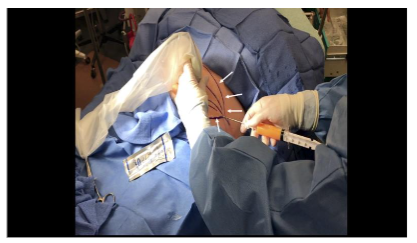

After sterile preparation and draping, the entry site was located approximately two fingerbreadths inferior and lateral to the umbilicus, superficial to the external oblique muscle.

The site was anesthetized using 2–3 mL of local anesthetic. Trajectory markings were made at the skin surface: one perpendicular to the long axis of the body, and two additional markings oriented approximately 45 degrees cephalad and caudally relative to the midline marking.

An optional tumescent technique was performed. A solution consisting of 500 mL sterile saline, 50 mL 2% lidocaine, and 1 mL of 1 mg/mL epinephrine was prepared. A small stab incision was made with an 11-gauge scalpel. Using a 17-gauge blunt-tipped infiltration cannula (Gallini Medical), 240 mL of tumescent solution was injected into the target adipose layer bilaterally under ultrasound guidance with the transducer positioned in short axis to the external oblique muscle. A 15–30 minute wait period would be allowed prior to lipoaspiration to facilitate anesthesia onset and vasoconstriction.

Once the tumescent technique was complete, a 13-gauge blunt-tipped lipoaspiration cannula (Gallini Medical, Mantova, Italy) attached to a 20 mL VacLok syringe (Merit Medical Systems, Inc., South Jordan, UT) was inserted using an in-plane technique under real-time ultrasound visualization. The cannula was introduced at an angle of less than 30 degrees to the skin surface. Negative pressure was created by retracting and locking the syringe plunger. Gentle lateral-to-medial and medial-to-lateral sweeping motions were used following the pre-planned trajectories to aspirate adipose tissue while always maintaining visualization of the cannula on ultrasound. If cannula visualization was lost, the ultrasound transducer was moved to reacquire the image rather than moving the cannula blindly. Approximately 5 mL of adipose tissue was harvested bilaterally from the abdomens of three cadavers for a total of six 5 mL collections (30 mL in total). Once aspirated, the tissue samples were sent to a laboratory for analysis.